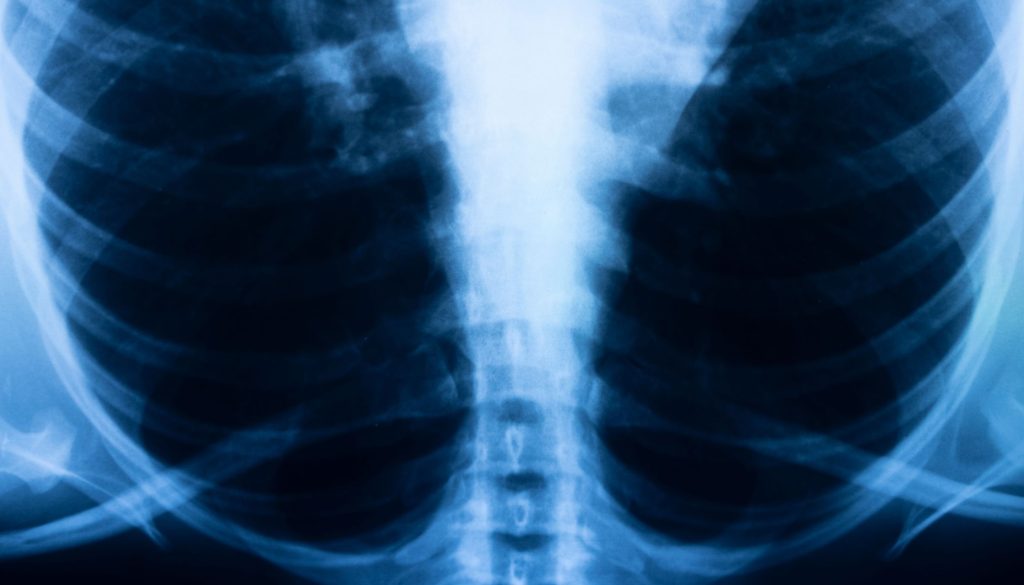

تُعد أمراض الرئة مثل التليف الرئوي والسدة الرئوية من التحديات الصحية الخطيرة التي تواجه العديد من الأفراد حول العالم. تؤثر هذه الحالات على جودة الحياة وقدرة الشخص على القيام بالأنشطة اليومية. في هذه المقالة، سنستعرض نصائح وتعليمات علاجية يمكن أن تساعد المرضى في تحسين حالتهم الصحية وسهولة التعامل مع المرض.

التليف الرئوي هو حالة تتسم بتكون ندوب في أنسجة الرئة، مما يجعل التنفس صعبًا ويؤثر على تدفق الأكسجين في الدم. الأسباب قد تشمل العوامل الوراثية، والتعرض للمواد الضارة، وبعض الأمراض المناعية.

تُعرف السدة الرئوية أيضًا بمرض الانسداد الرئوي المزمن (COPD)، وهو مرض تنفسي يتضمن مشاكل في تدفق الهواء بسبب التهابات الشعب الهوائية وانتفاخ الرئة. يرتبط التدخين بكونه السبب الأساسي، إلى جانب عوامل أخرى مثل التلوث البيئي.